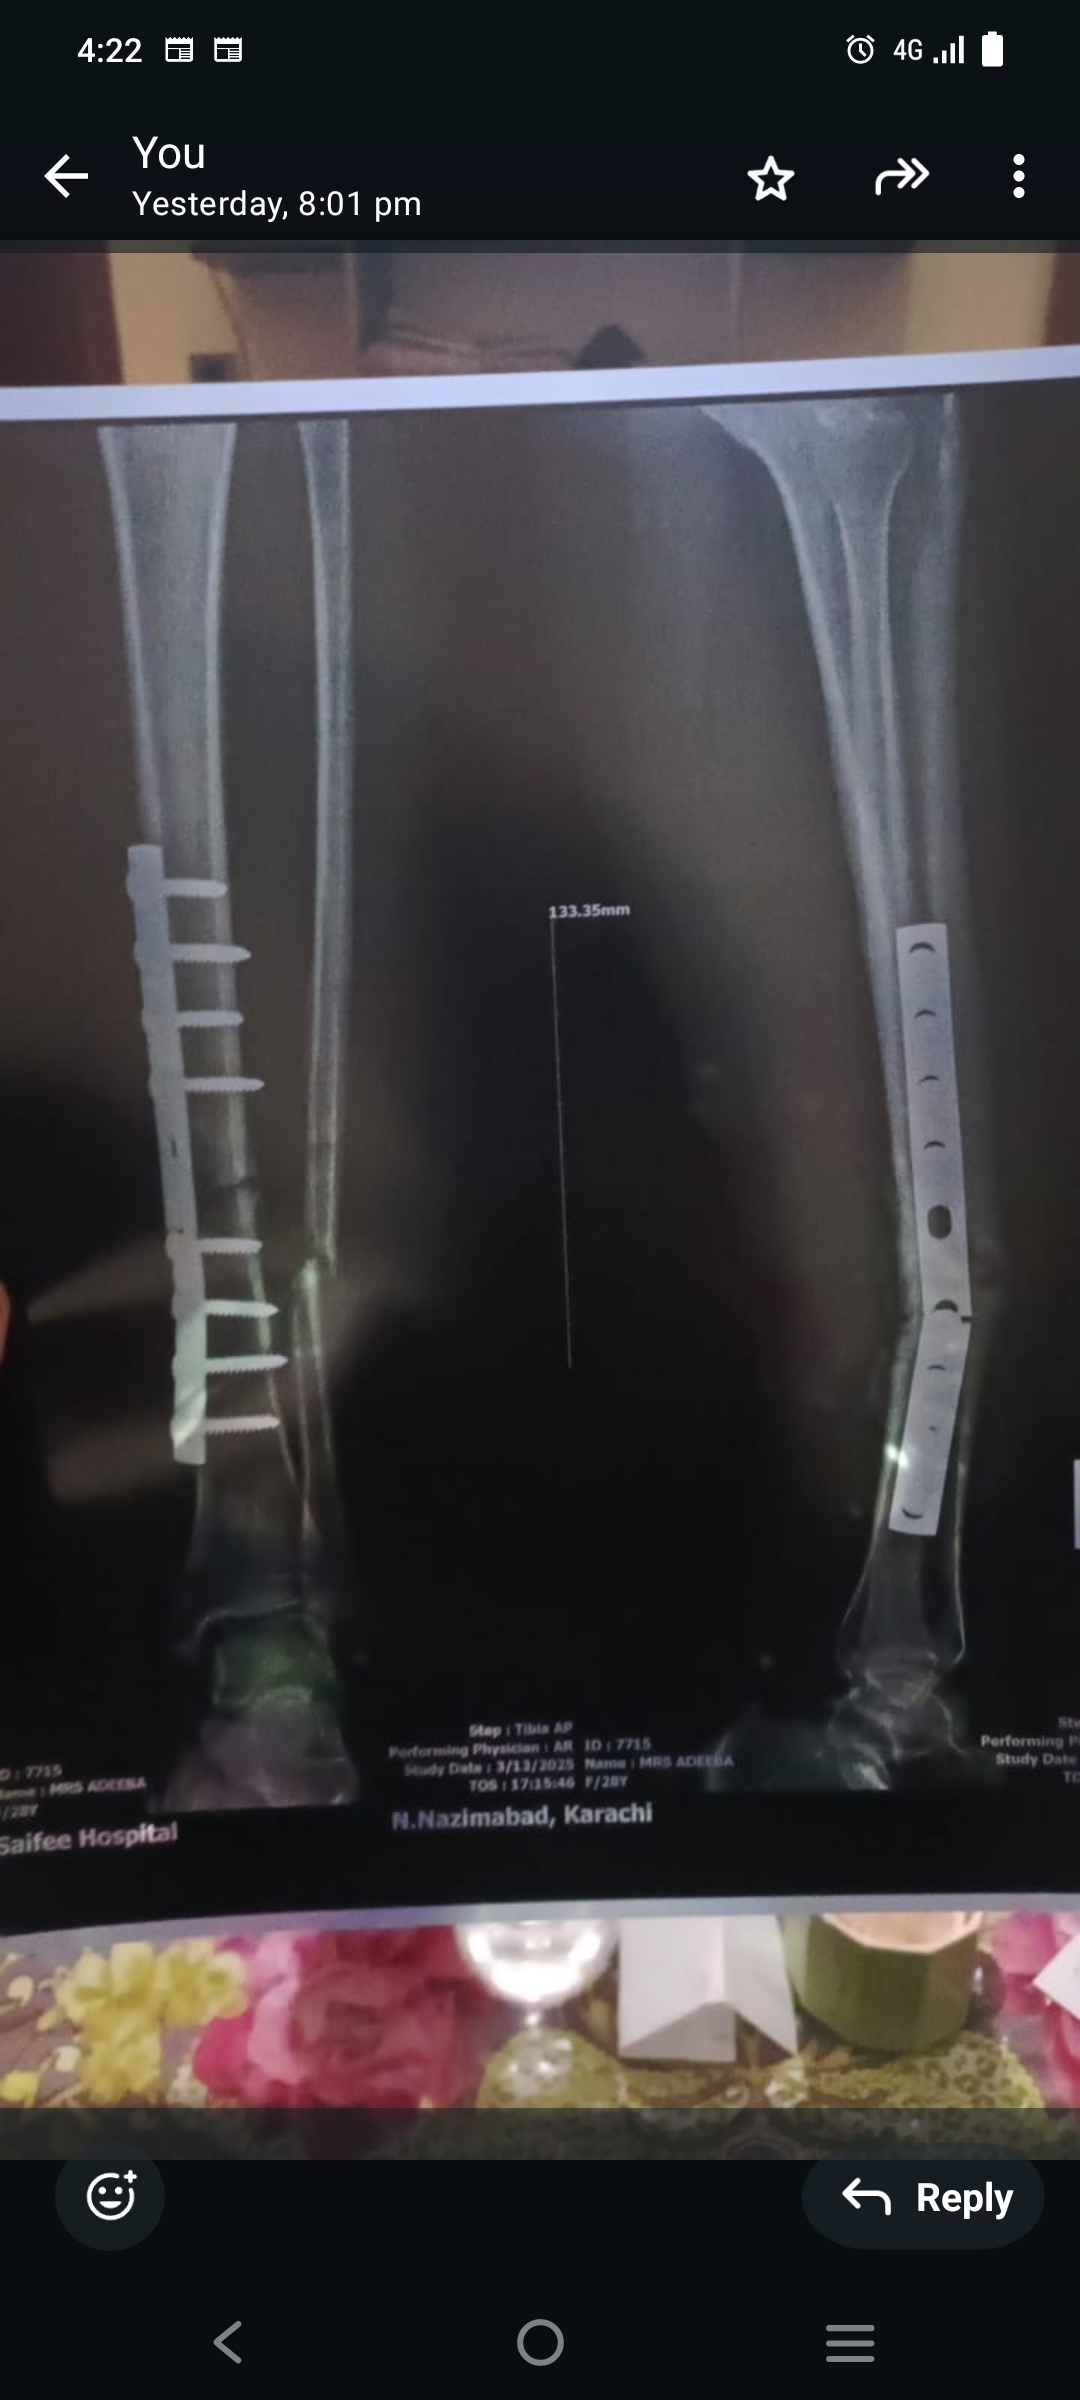

Sir 6 mahine pehle plate dali thi motorwey pe accident howa the os key bad plate Sahi recent Kal sey bohat pain the Xtra karwaya to pata Chala hai plate toot gayi hai meherbani farmakey rehnumai farmaden

You need a redo surgery

need surgery

removal of plate

imil nail

it definitely needs another surgery